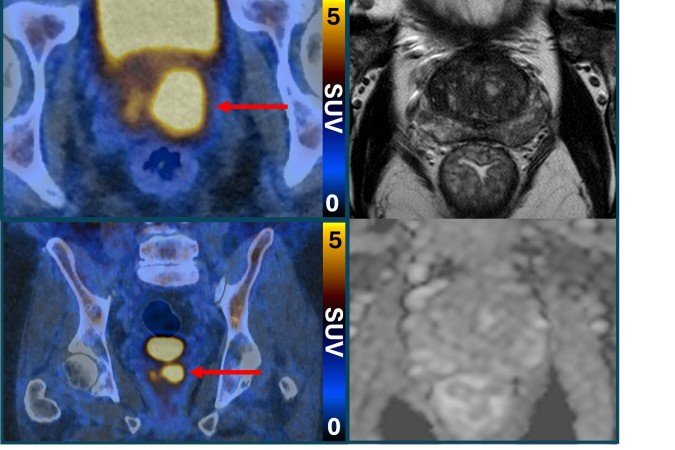

O exame PET/CT (tomografia por emissão de Pósitrons/tomografia computadorizada) com PSMA identifica células agressivas presentes na próstata, que são potencialmente prejudiciais e podem precisar de tratamento. Isso é possível graças a uma molécula que se liga a essas estruturas e as faz brilhar, aparecendo como pontos luminosos na imagem. O estudo afirma que isso também pode ajudar a reduzir o risco de sobrediagnóstico.

O ensaio descobriu que a tomografia por emissão de pósitrons (PET/CT) com PSMA podia identificar pessoas que não tinham câncer ou cujo tumor era de tão baixo risco e com crescimento tão lento que provavelmente nunca causaria danos. Esses pacientes não precisaram de biópsia. A nova abordagem reduziu pela metade o número de pessoas submetidas ao exame invasivo, sem deixar de detectar nenhum câncer maligno.

A abordagem também beneficiou os pacientes que ainda precisavam de biópsia. Os resultados da tomografia garantiram que o procedimento fosse direcionado às áreas suspeitas identificadas no exame de imagem, a fim de minimizar complicações e aumentar a precisão.